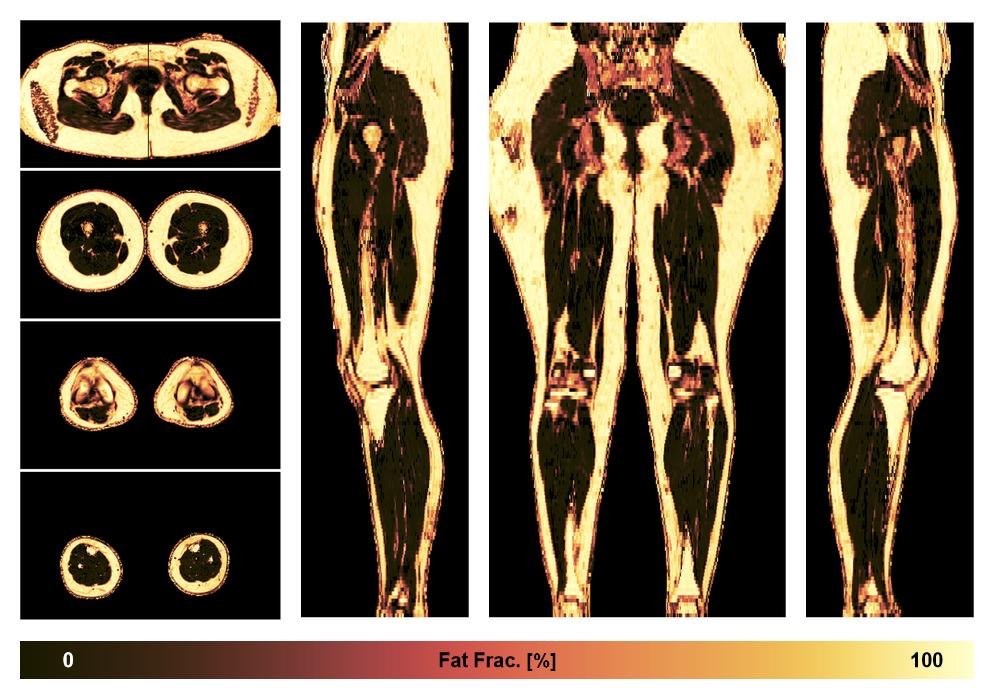

• Fat fraction

The fat fraction of the lower extremity obtained from the dixon reconstruction for muscle water fat quantification.